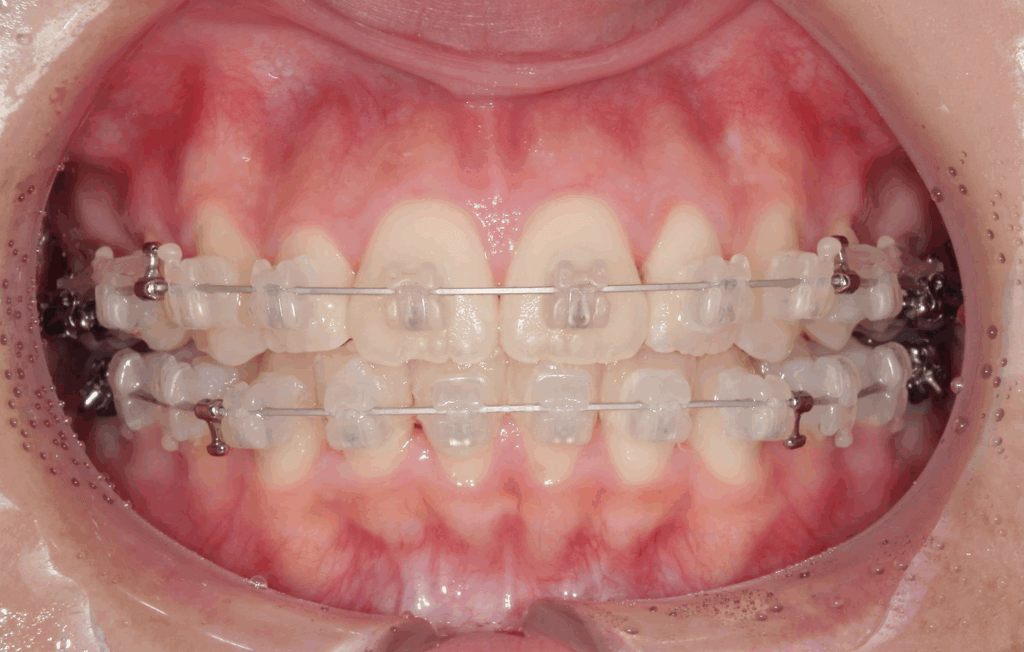

治療装置について

今回の治療では、見た目にも配慮して白い「セラミックブラケット」とホワイトワイヤーを使用しました。透明感のあるブラケットと白いワイヤーの組み合わせは、金属の装置に比べて目立ちにくく、お仕事中や日常生活でも気になりにくいのが特徴です。